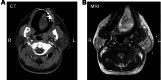

Case presentation: A 33-year-old Chinese man presented with a progressively enlarging mass at the base of his left tongue. Contrast-enhanced computed tomography and magnetic resonance imaging revealed an augmented soft tissue mass in the left jaw region with indistinct boundaries, enlargement of cervical lymph node of uncertain etiology, and no evidence of distant metastasis. A transoral needle biopsy from the mass pathologically revealed low-grade mucoepidermoid carcinoma. Complete transoral excision and cervical lymph node dissection were performed, followed by reconstruction with an anterolateral thigh free flap. Examination of the obtained surgical specimen confirmed low-grade mucoepidermoid carcinoma with MAML2 gene fusion in the base of the tongue. The tumor was removed with negative margins, and the cervical lymph nodes were free of disease. The patient had an uneventful recovery and showed no evidence of recurrence or metastasis at 40 months of follow-up.